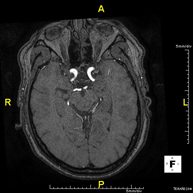

- Intracranial MRI angiography

This non-invasive diagnostic procedure uses an electromagnetic field and radio waves (from a transmitter and receiver) to acquire high-definition anatomical images of the cerebral arteries. It is a radiation-free procedure. In most cases, paramagnetic contrast (gadolinium) is required. It enables non-invasive angiographic studies using a gadolinium injection, with subsequent 2D and 3D reconstruction using specialised workstations. Indicated for: vascular malformations, cerebral artery aneurysms, arteriosclerosis.